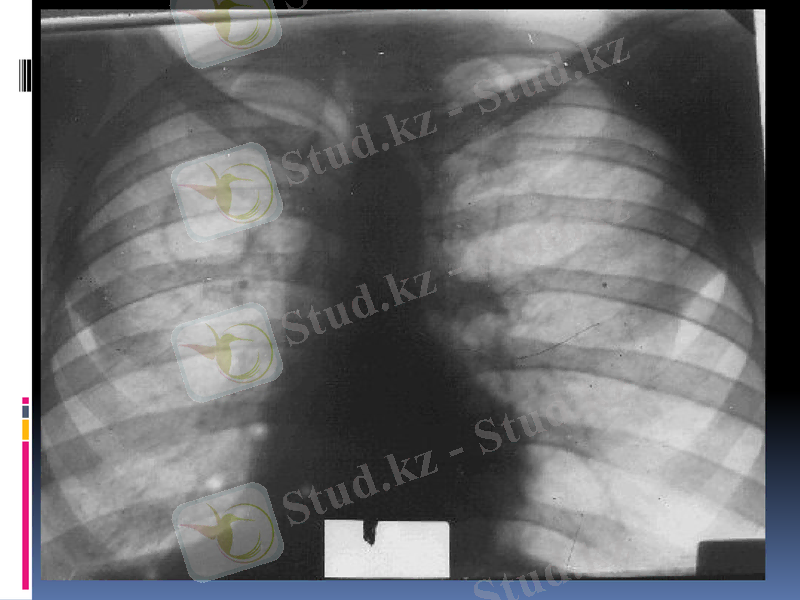

Кавернаның негізгі рентгенологиялық белгісі перпендикулярлы проекцияда сақталатын тұйық сақина тәрізді көлеңке болып табылады.

Сақина тәрізді көлеңкемен шектелген өкпе бөлігі кавернаның терезесі деп аталады. Айналасындағы өкпе тініне қарағанда, ол мөлдірлеу болады. Өкпенің элементтері негізделген құрылымдарында кавернаның терезесінде көлеңкелер көрінбейді